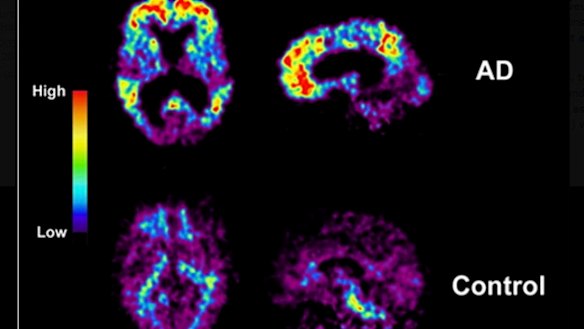

Scans of an Alzheimer's sufferer.

We know the plaques are made of a protein called beta-amyloid. They block neurons from talking to each other. Another protein called tau also appears to be involved, forming into "tangles" that cut off the transport system that ferries nutrients within brain cells.

Both plaques and tangles form first in the areas of the brain important to memory and learning and then gradually progress to other regions, killing neurons as they go. Patients lose their memory first, and then other functions progressively deteriorate.